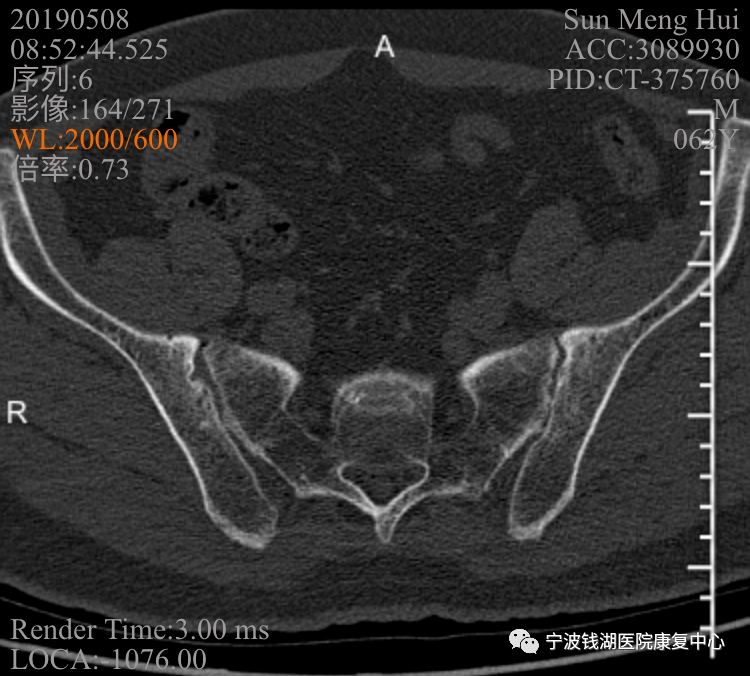

2019-05-8:骶髂关节ct:双侧骶髂关节炎,请结合临床.

骶髂关节ct